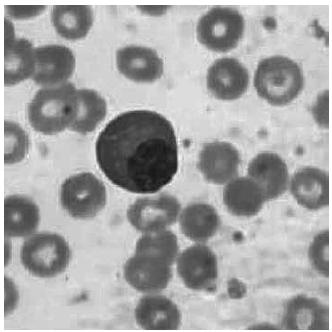

Paciente masculino, 56 anos, com fortes dores ósseas e inchaço nas pernas, realizou exames para investigação. Apresentou valores de lactato desidrogenase elevado 350,0 UI/L e, no hemograma, encontrou-se a celularidade atípica ilustrada a seguir.

Imagem: Lâmina de esfregaço sanguíneo

(Imagem gentilmente cedida pelo Laboratório de Análises Clínicas da FMABC do Centro Universitário FMABC)